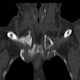

Женщина за 50 лет. Жалобы на припухлость и болезненость в области правого грудинно-ключичного сочленения. Принял решение не проводить рентгенографию, а сразу направить на КТ.

Хорошо. Тогда - мнение врача КТ, с коим я абсолютно согласен, - асептический некроз грудинного конца ключицы.

Не против того, что в какой то мере здесь присутствуют и явления артрозо-артрита, но ТАКИЕ изменения структуры грудинного конца ключицы, да еще и с наличием секвестров, вряд ли были бы характерны только для артроза.

1.Клинически при осмотре - припухлость, болезненная, без особых наружных признаков воспаления, существующая несколько месяцев, медленно прогрессирующая в размерах, ограничение движения в плече (из за болезненности в ключично-грудинном сочленении).

Не вижу явных признаков некроза, а вот изменения суставной поверхности в виде изьеденности по ключице и грудине пристутствуют. Единственное минус - нет расширения суставной щели. То, что принимаете за секвестры, скорее всего, являются изменениями края кости за счёт воспаления окружающих тканей: ревматоидный артрит (к примеру). В таких случаях проверяю себя УЗИ (изменения мягких тканей).

1. Если бы не вовлечённость значительной части ключицы (кости), тоже бы заключил артрозо-артрит.

2. Я не врач КТ, но. имея некоторый рентгенологический и клинический опыт прихожу к выводу. что сия ситуация выходит за рамки артрозо-артрита, а первое мнение было именно врача КТ - об асептическом некрозе.

4. Меня, в первую очередь, смущает тоже большой обьем поражения кости, что не характерно для артроза.

Вижу подобную картину не так уж и редко и трактую это как артроз-артрит. Причем, вижу это в ста процентах случаев как случайную находку (пациенты с ДТП и прочие травматики) и без всякой клиники в анамнезе. Убедительных данных (признаков) за ас.некроз тут не вижу. У меня нет наработок, какие изменения происходят в итоге в костях суставов при зазличных видах артритов. Вероятно, что разница может быть очень серьезная.

Ладно, предположим. Асептический некроз. Но сейчас-то мы видим явную дегенератику + склеротическое уплотнение + клиника. Чем не банальные артрозоартритные дела с морфологической декомпенсацией? Или мы говорим об исходе асептического некроза?